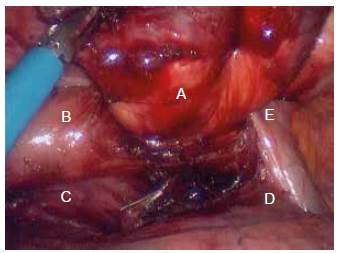

Mujer de 72 años de edad, con cuadro clínico de un año de disfagia y atragantamiento con alimentos sólidos, que había requerido tratamiento endoscópico. Se realiza endoscopia de vías digestivas altas que documenta un divertículo esofágico en tercio medio, y manometría esofágica de alta resolución, sin trastorno motor. El esofagograma (figura 1) y la tomografía computarizada de tórax (figura 2) muestran un divertículo en tercio medio de esófago, lateral derecho, de 7 cm de diámetro y base de 2.5 cm de diámetro. De manera programada se lleva a cabo diverticulectomía esofágica por toracoscopia, en decúbito prono (figura 3), sin complicaciones.

Figura 3 Divertículo (A) y esófago distal (B), en relación anatómica con las venas pulmonares derechas (C), bronquio principal derecho (D) y cayado de la vena ácigos (E).